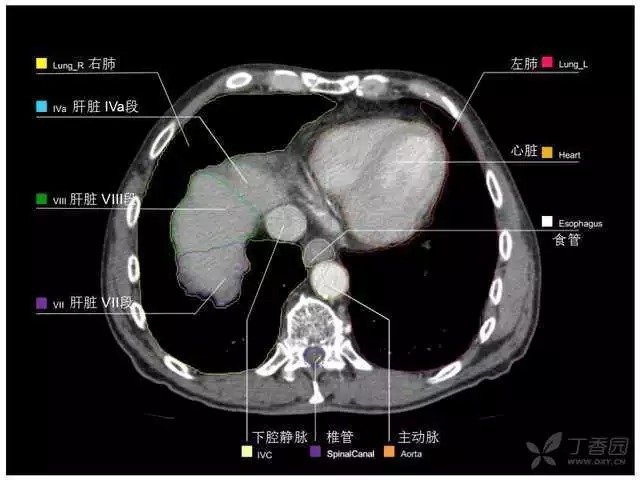

腹部肝脏高清CT断层的图谱

全腹部高清CT图谱,淋巴结彩色图谱,血管解剖图谱大汇总!

肝段,肝内管道的分布规律

美国放射学会ACR官网,对肝脏的区域和节段解剖学概述